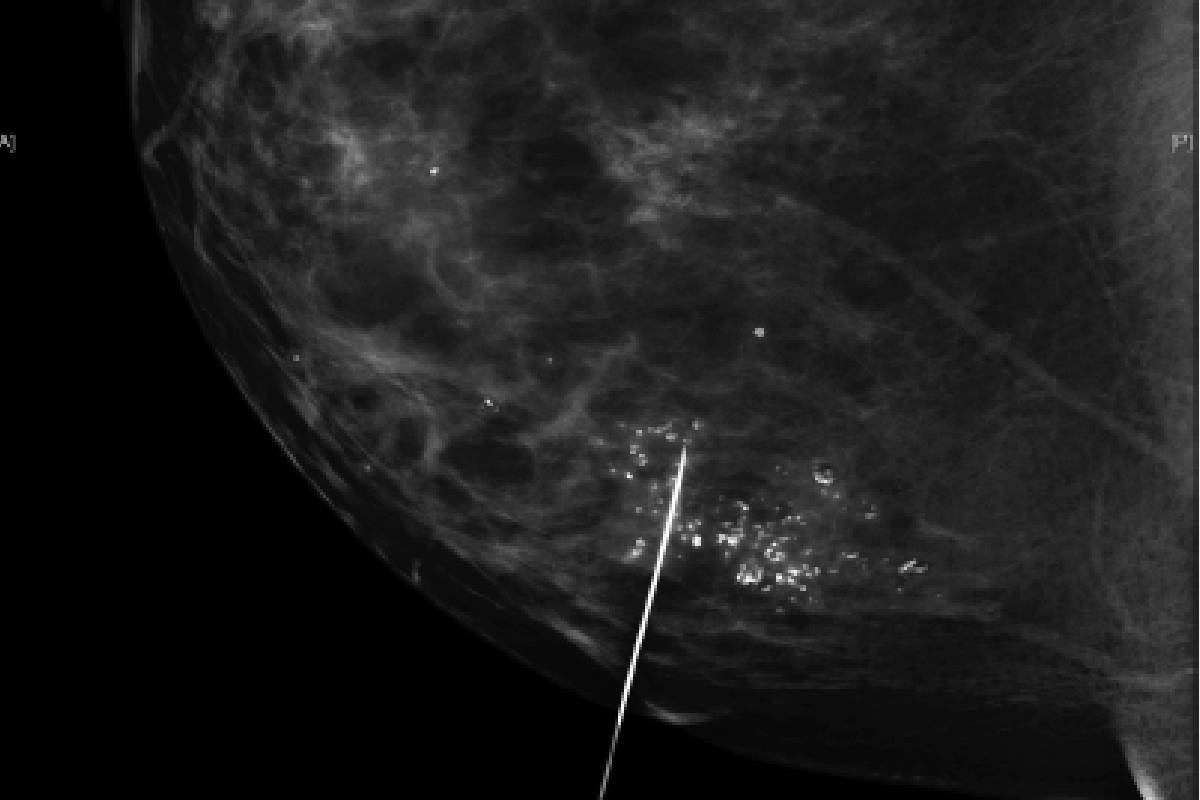

Guide Wire Localization Surgery by Dr. Indrani Joshi is a highly precise technique used to accurately locate and remove abnormal breast tissue that cannot be felt during a physical examination but has been detected through imaging like mammography or ultrasound. In this procedure, a radiologist places a thin wire into the breast to mark the exact location of the suspicious area, enabling Dr. Indrani Joshi to precisely remove the targeted tissue while preserving as much healthy breast tissue as possible.

This procedure is commonly performed for diagnosing or treating early-stage breast abnormalities, such as suspicious lumps, nodules, or microcalcifications. With a strong focus on precision, patient comfort, and safety, Dr. Indrani Joshi ensures that guide wire localization leads to accurate results, minimal discomfort, and faster recovery, ultimately contributing to better surgical outcomes and peace of mind for every patient.